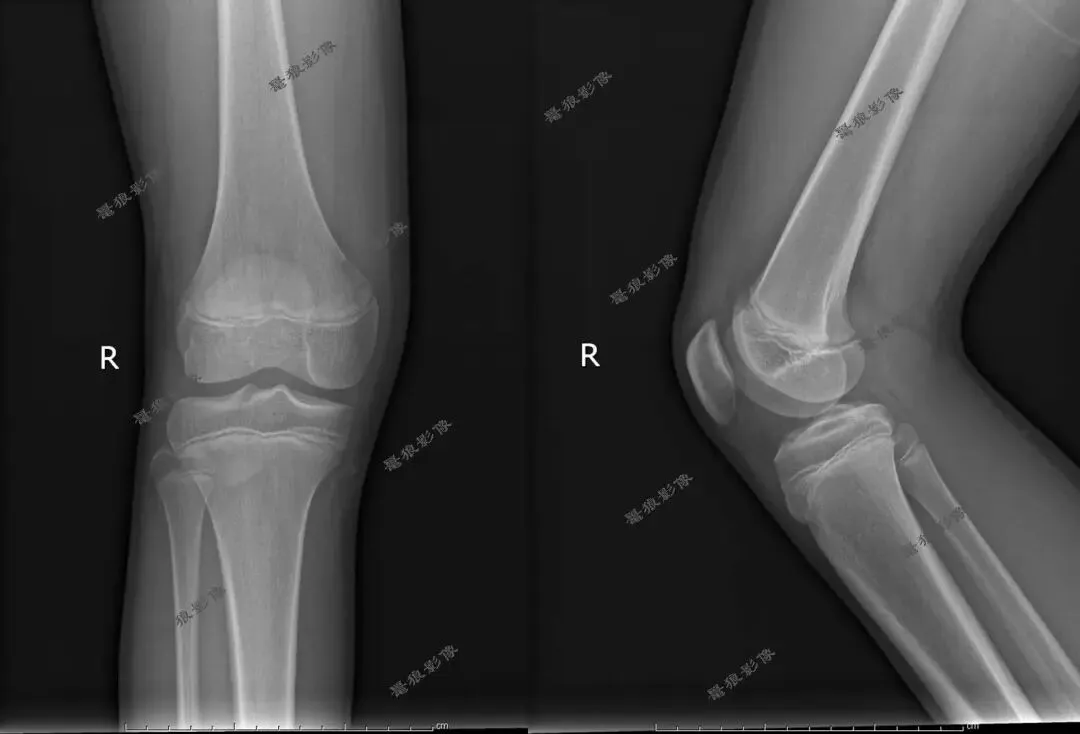

M,13y。左膝疼痛月余,近日加重就诊。

X线平片(双侧):

考虑左胫骨结节骨软骨炎,请结合临床,建议进一步检查。

X线:早期可见髌韧带附着点软组织肿胀、髌韧带增厚;中期胫骨结节骨骺密度增高、不规则、边缘模糊,可出现骨碎片;修复期可见骨骺融合或遗留游离骨片。